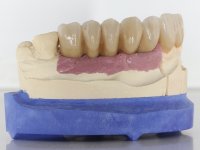

A temporary acrylic bridge made in the laboratory with 7 elements was made, with teeth 11,21, 25 and 26 as pillars. The old bridge was removed and tooth 24 was extracted. The provisional bridge after relining was cemented in the mouth. Two implants were placed in the teeth 22 and 24 and 3 months after this intervention an impression was made to make a temporary bridge screwed over the implants and cemented to the teeth. The bridge was placed in the mouth and teeth 25 and 26 were extracted. 3 months later, surgery was performed to fill the maxillary sinus and 6 months later the implant was placed in the location of tooth 26. After osseointegration of this implant, the final impression was made for the final work. The bridge over the implants was permanently screwed on and the bridge over the teeth was cemented with resin-reinforced glass ionomer cement.